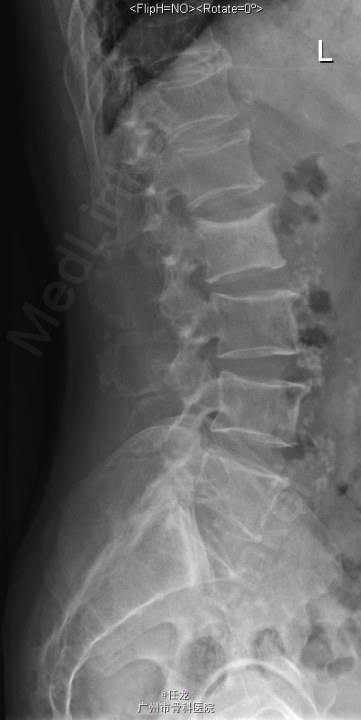

主诉:前列腺癌术后8年,反复腰痛半年,加重2周。 病史:患者8年前曾诊断为前列腺癌,并在外院行手术治疗,并多次放疗,一般坚持门诊复查。半年前出现腰部疼痛,为持续性疼痛,休息后无缓解,无双下肢麻木疼痛。最近两周加重明显,影响睡眠。遂至门诊就诊,门诊MRI考虑:前列腺癌腰椎转,故收入院作进一步诊治,患者一般情况较差。

查体:L2-L4棘突及棘旁轻度叩压痛。四肢感觉、肌力及肌张力正常。双侧坐骨神经出口处无轻压痛。双侧直腿抬高试验(-),双侧股神经牵拉试验(-)。双侧膝反射及踝反射未引出,双侧踝阵挛阴性。双侧Babinski 征及Oppenheim 征(-)。 辅助检查:PSA:73.22ng/ml ↑。腰椎影像学检查如下。

诊断:1. 前列腺癌腰椎转移 2.前列腺癌切除术后 处理:入院后完善相关检查,术前给予对症治疗,科里术前讨论决定:拟行手术:L2-4经皮穿刺活检+术中放疗+椎体成形术。